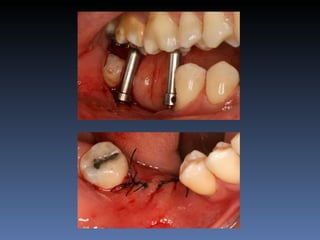

BOX 3

José Luiz Peretti

Idade – 67 anos

Sexo – Masculino

Raça – Caucasiana

ASA – II

Data- 23-04-2012

Diagnóstico: Desdentado parcial maxila

Plano de tratamento: Reabilitação da área desdentada

1.4,.1.5 com instalação de 2 implantes endo-ósseos

para reabilitação protética fixa .

O meu primeiro Implante